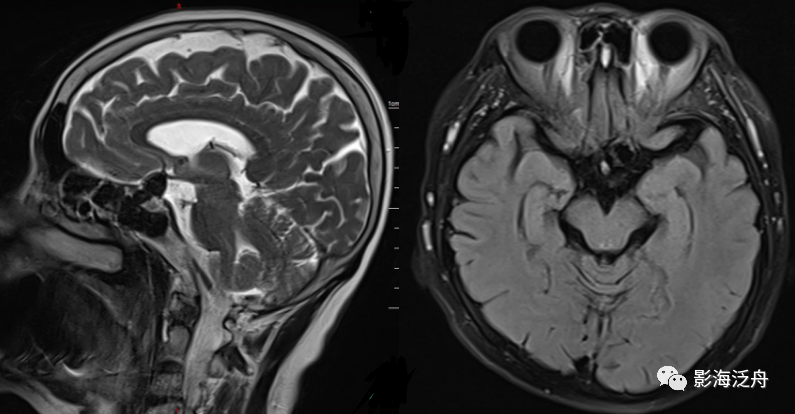

病例三:患者男,67岁,头晕伴头痛1周,既往有脑梗死病史,血压145/95mmHg,神经系统查体无殊。

病例三:静脉窦血栓。正常情况下,上矢状窦在SE序列(T1WI)和FSE(T2WI)序列上均呈流空低信号(绿箭头),本例中上矢状窦呈等高信号(红箭头),结合患者头痛病史,应考虑上矢状窦血栓。